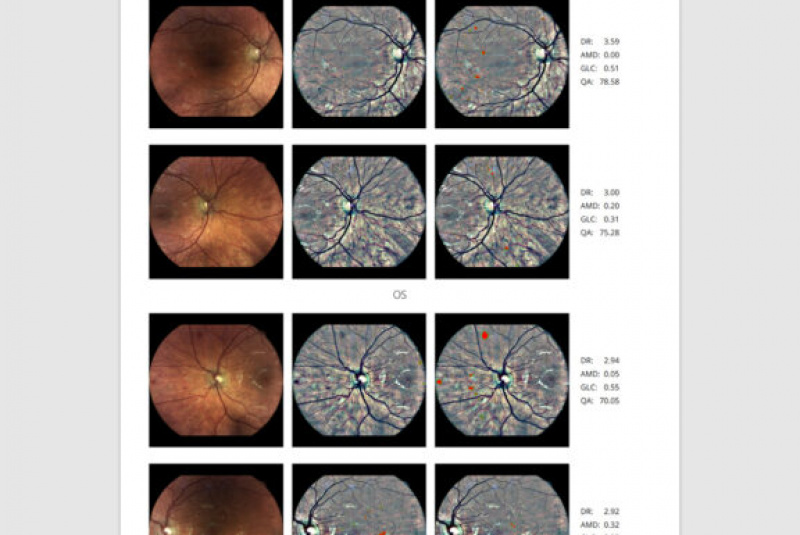

Fundus kamera iCare DRSplus urobí celkovo 4 vysoko kvalitné snímky (dve z pravého a dve z ľavého oka), ktoré sa automaticky ukladajú na cloud a posielajú sa na spracovanie AI - umelej inteligencii. Report je dostupný ihneď a ten je možné prekonzultovať s pacientom počas tej istej návštevy u lekára.

Kamera iCare DRSplus spoločne pomocou softwaru využívajúceho umelú inteligenciu iCare RETCAD® vykonáva vyhodnotenie skríningu diabetickej retinopatie, ktorá šetrí váš drahocenný čas, umožňuje včasnú intervenciu a pomáha poskytnúť včasnú zdravotnú starostlivosť. Anlýza pomocou iCare RETCAD® nenahradzuje vyšetrenie zdravotného stavu očí.

Správa obsahuje

- stupnicu závažnosti ochorenia pre diabetickú retinopatiu, VPMD a podozrenie na glaukóm

- v prípadoch kedy je to potrebné, AI odporúča poslať pacientov na ďalšie vyšetrenie k špecialistovi

- infračervené mapy zvýrazňujúce svetlé a červené lézie/poškodenia

- hodnotenie kvality vstupných obrázkov